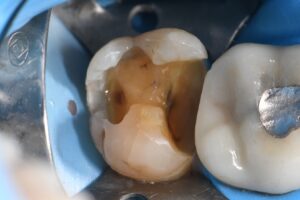

March 10, 2026 (Afternoon tea pics 2341.3: Kerr Simplishade | Rhondium DME | Garrison Dental Solutions – North America) Getting d o w n with DME. #RhondiumDME #KerrSimplishade #GarrisonCompositight Previous Post